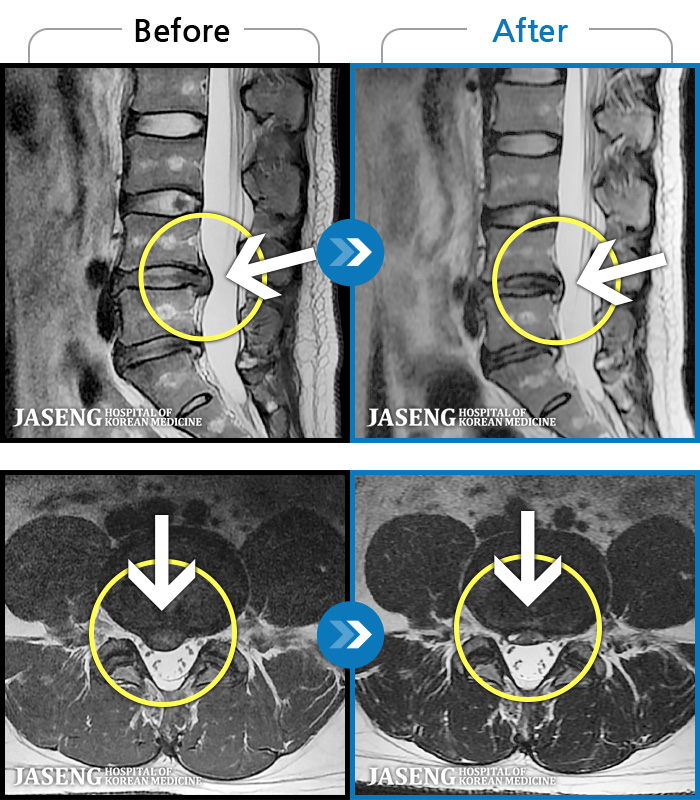

허리디스크

안산 · 조창현 원장

심한 허리 통증으로 내원

촬영시기

2025.04.22 ~ 2025.11.03

2025.11.07

조회수 168

허리 통증 및 오른쪽 다리로 내려가는 심한 통증으로 혼자 보행 어려워 응급 내원

2019.09.21 ~ 2021.10.05

2021.10.08

조회수 2,669